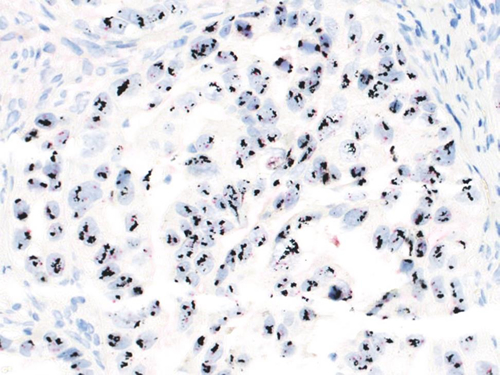

内視鏡検査、婦人科、整形外科、皮膚科などで採取した生検材料や、手術で摘出された腫瘍などが対象となります。ホルマリン固定、脱脂、脱水、パラフィン包埋後、2ミクロン(1,000分の2ミリ)に薄切りしガラスに貼付け染色後、病理専門医が顕微鏡で観察し、診断します。通常のヘマトキシリンエオジン(H.E.)染色だけでは判断し難い症例では、特殊染色や標本上で抗原抗体反応を起こし細胞の詳細を検索する免疫抗体法を行い、診断します。

近年、化学療法や分子標的治療の開発が進み、

がんの種類、進行度に沿った最適な手術や治療法が選択されるようになり、今まで以上に病理専門医、細胞検査士が治療法選択の判断に直結する機会が増加しています。当院では、2011年から術中迅速診断において免疫化学的検索が必要とされる症例においては、電界非接触撹拌迅速免疫染色技術(R-IHC)を併用し、タイムリーで精度の高い病理診断情報を手術場の臨床医と患者さんに提供できるよう努めています。

Ⅴ.分子標的治療薬の選別を目的とした遺伝子検査 (DISH法)

HER2過剰発現が確認された乳癌、胃癌、大腸癌、唾液腺癌に対する分子標的治療薬としてトラスツズマブ(ハーセプチン)が承認されています。この治療薬の投与対象選別のための検査方法として2011年から保険適用となった「DISH法(Dual Color in situ hybridization)」により、対象遺伝子の増幅比を判定しています。

1) 電解撹拌迅速免疫染色装置技術(R-IHC)を併用した術中迅速診断